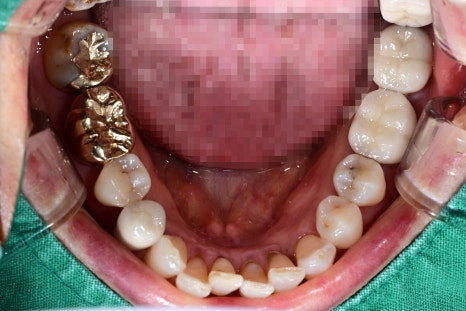

① 손상된 치아 제거

필요한 경우에만 진행되며,

흔들리는 치아나 염증이 심한 치아는 먼저 제거합니다.

사례 환자분도 오른쪽 위 어금니 두 개를

발치한 후 다음 단계로 넘어갔습니다.

② 잇몸뼈 회복 또는 뼈 보강

잇몸뼈가 약하면 임플란트가 단단히 고정되기

어렵기 때문에 뼈를 보완하는 과정이 필요할 수 있습니다.

이는 임플란트 안정성을 높이기 위한 표준적인 과정입니다.

③ 임플란트 식립(나사 심기)

국소마취로 진행되며 비교적 짧은 시간 안에 끝납니다.

환자분들도 흔히 “생각보다 금방 끝났다”고

말씀하시는 편입니다.

위 사례에서도 두 개의 어금니 위치에

임플란트를 심는 수술이 안정적으로 마무리되었습니다.